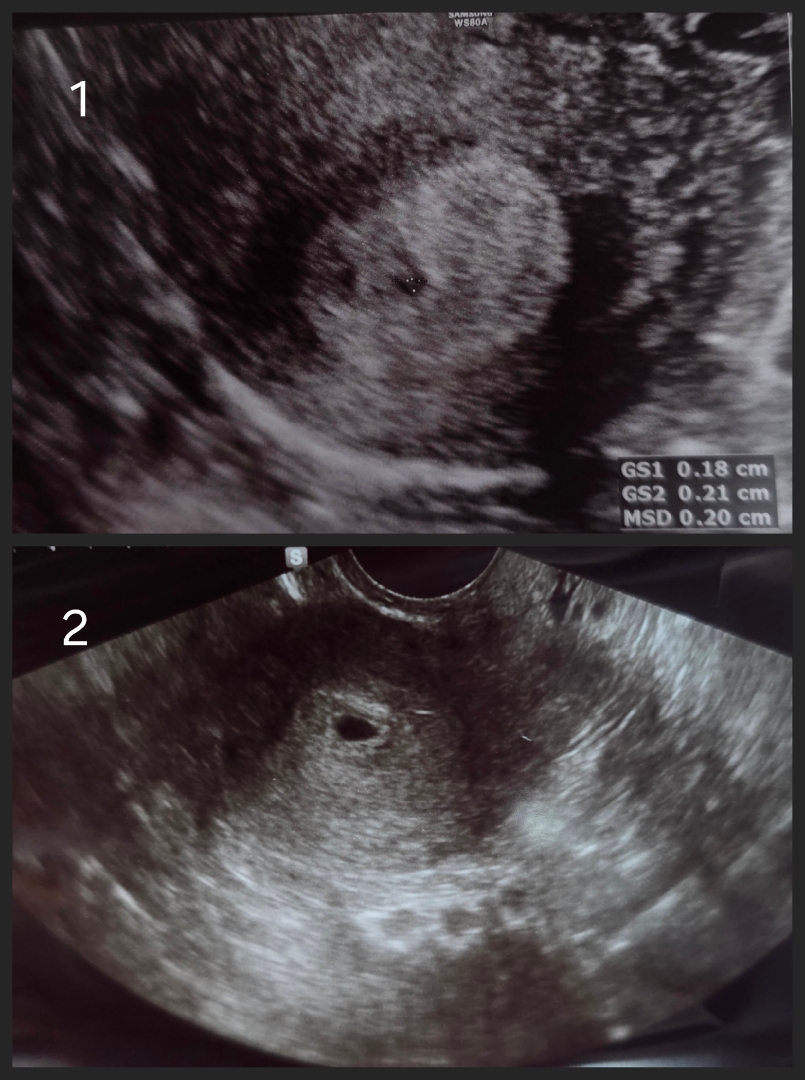

8월6일에 막생 했고 9월13일에 임테기 두줄 확인해서 16일에 동네 산부인과가서 초음파 찍었는데(1번 사진) 5주차고 내년 5월13일이 출산예정이라고 하셨어요 지인들이 5주차 초음파사진 보여줄땐 아기집이 크던데 전 너무 작아서 선생님께 여쭤봤더니 5주는 저 크기가 맞다고 하셔서 그렇구나 했는데.. 오늘 배랑 허리가 너무 아파서 회사 앞 산부인과가서 초음파 찍었는데(2번 사진) 일주일이 늦어서 이제 5주차 진입했다고 하시더라구요ㅠ 그래서 출산예정일도 5월20일로 늦어지고 원랜 오늘이 6주1일차인데 갑자기 5주1일차가 되어버렸습니다 이렇게 늦어지면 유산하는 경우도 있다고하는데 괜찮을까요? 처음 갔던 병원에서 다음주 27일에 심장소리 듣기로 했는데 너무 걱정되네요ㅠㅠ